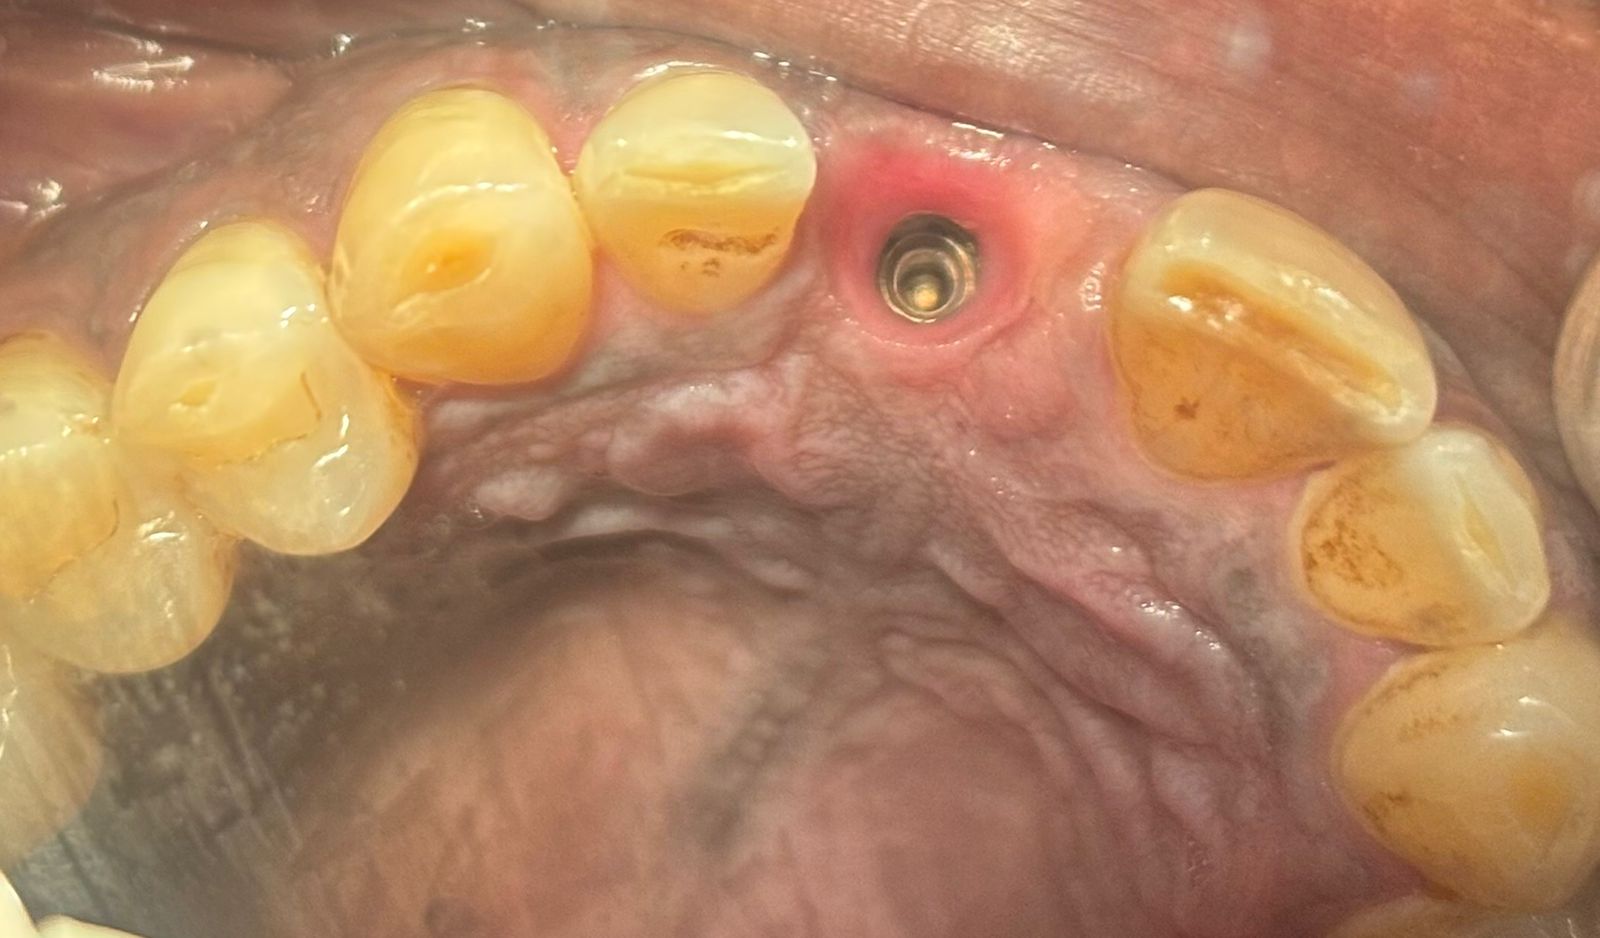

Implant bone with screw

With no records available, identifying the internal hex connection of Rajesh's implant required a hands-on, systematic approach. Different implant systems use different internal hex sizes — the small hexagonal socket that the screwdriver fits into when tightening the abutment screw. The wrong driver will either not engage at all, or worse, strip the connection.

At Crown Dental Care, we maintain a comprehensive master hex driver kit — a set of calibrated screwdriver tips covering the full range of hex sizes used across major implant systems worldwide. Working methodically through the kit, the attending clinician tested each driver against the abutment screw until finding the one that seated cleanly, with no rocking or play.

Identified Hex Size

The internal hex was confirmed as 1.25 mm — consistent with several widely used implant platforms. The abutment screw was re-torqued to the appropriate specification, the crown was re-cemented, and occlusion was checked and adjusted. Rajesh left the clinic with a secure, functional smile.